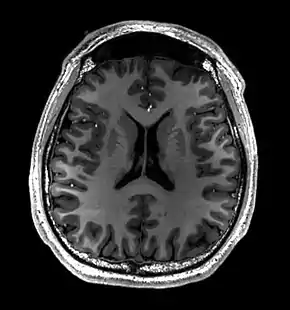

Magnetic resonance imaging of the brain uses magnetic resonance imaging (MRI) to produce high quality two-dimensional or three-dimensional images of the brain and brainstem as well as the cerebellum without the use of ionizing radiation (X-rays) or radioactive tracers.